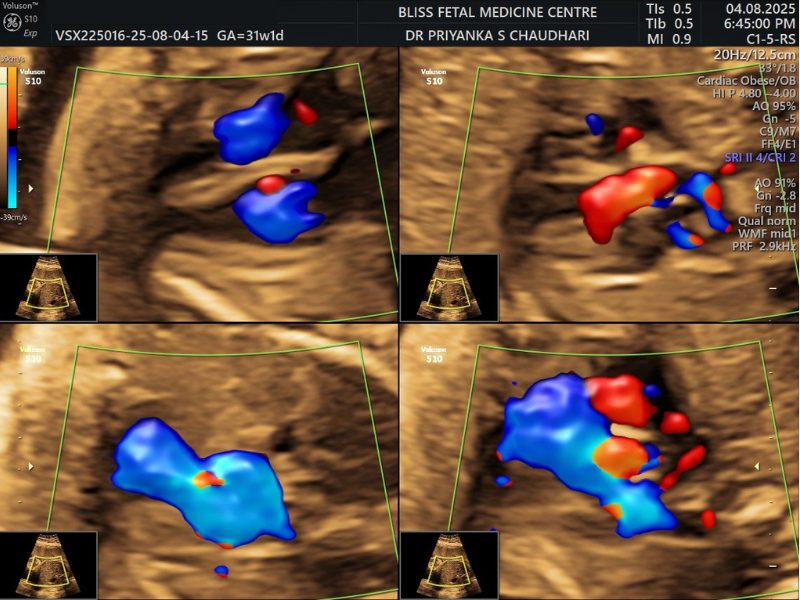

5. Fetal Echocardiography

This painless ultrasound test helps see the baby’s heart structure and its functioning. If an abnormality is detected during the routine scan or if the routine obstetrical ultrasound did not clearly show the baby’s heart, Fetal Echocardiography can help.

When Is It Performed?

- It is performed between 18 to 24 weeks in the second trimester.

- It can be performed if there is a related family history or the baby has a genetic disorder.

- It is also needed if the mother has a condition that increases the risk to the baby’s heart.